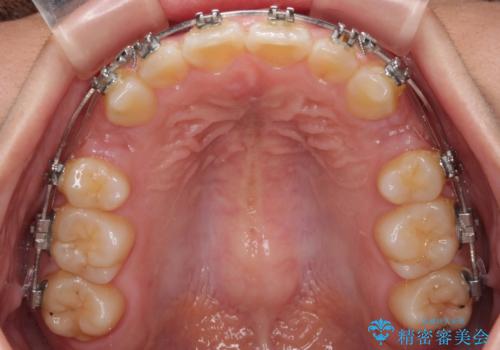

- 矯正装置

- メタルブラケット

上顎小臼歯の歯根が左右ともに大きく曲がっており、スペースクローズに時間がかかってしまいました。